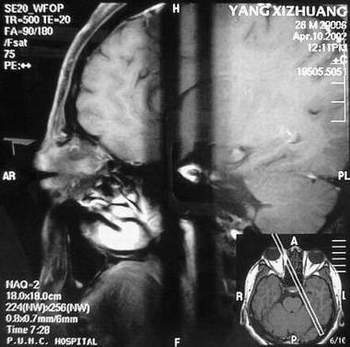

MRI及增强结果如下:

患者压颈及其它Valsava试验结果阴性。从MRI分析,在T1、T2、T+C检查该支血管均为明显流空现象,说明该血管血流速度很快,而从走行和分布看,眼上静脉可能性很大。也许也不能除外异常的眼动脉或异常血管。眶内主要可能的血管病变包括颈内动脉海绵窦瘘(高流窦)、AVM、眼眶静脉曲张、海绵状血管瘤、静脉性血管瘤、毛细血管瘤和眶内动脉瘤。。 1、颈内动脉海绵窦瘘:该患者临床有一部分支持该诊断。但从影像分析,海绵窦未见明显扩张;眼外肌未见明显充血扩张的长T1、长T2信号;颈内动脉海绵窦瘘常可见继发到血栓,可见到短T1、长T2的血栓信号。 2、眼眶静脉曲张:该疾患一般常见于小儿。该患大多数会出现Valsava试验阳性,间歇性突眼。不符合该患。影像学检查,于曲张静脉内常可见血栓和静脉石。所以不符合该患。 3、AVM:患者目前的影像学资料尚不全面,但可符合该诊断。临床上改病常见于30岁左右年轻人,单侧发病,于本患较符合。问题在于临床没有明确的血管杂音,似乎难以解释。 4、该患影像学与海绵状血管瘤差别很大,所以可基本排除此诊断。 5、静脉性血管瘤和毛细血管瘤:MRI中等T1、长T2信号,较易与本病鉴别。 6、眶内动脉瘤:我觉得患者并不能排除本病,但同样,由于波动性阴性,似乎也难以解释。 纵上所述:本人觉得,患者AVM可能性较大,同时不能除外眶内动脉瘤。 关于进一步检查,我觉得DSA价格过于昂贵。是否可先进行彩色多普勒检查,首先可以明确是静脉系统还是动静脉瘘抑或是动脉瘤。第二步,可进行MRA检查,可以清楚地显示海绵窦地相关关系,并可借此诊断或排除颈内动脉海绵窦瘘。如还需第三部检查,可进行MRV检查,对静脉系统进一步评价。三种检查总共的费用2000多圆,但给予我们的信息量已经很丰富了。 敬请各位医师提出自己的见解。 谢谢!